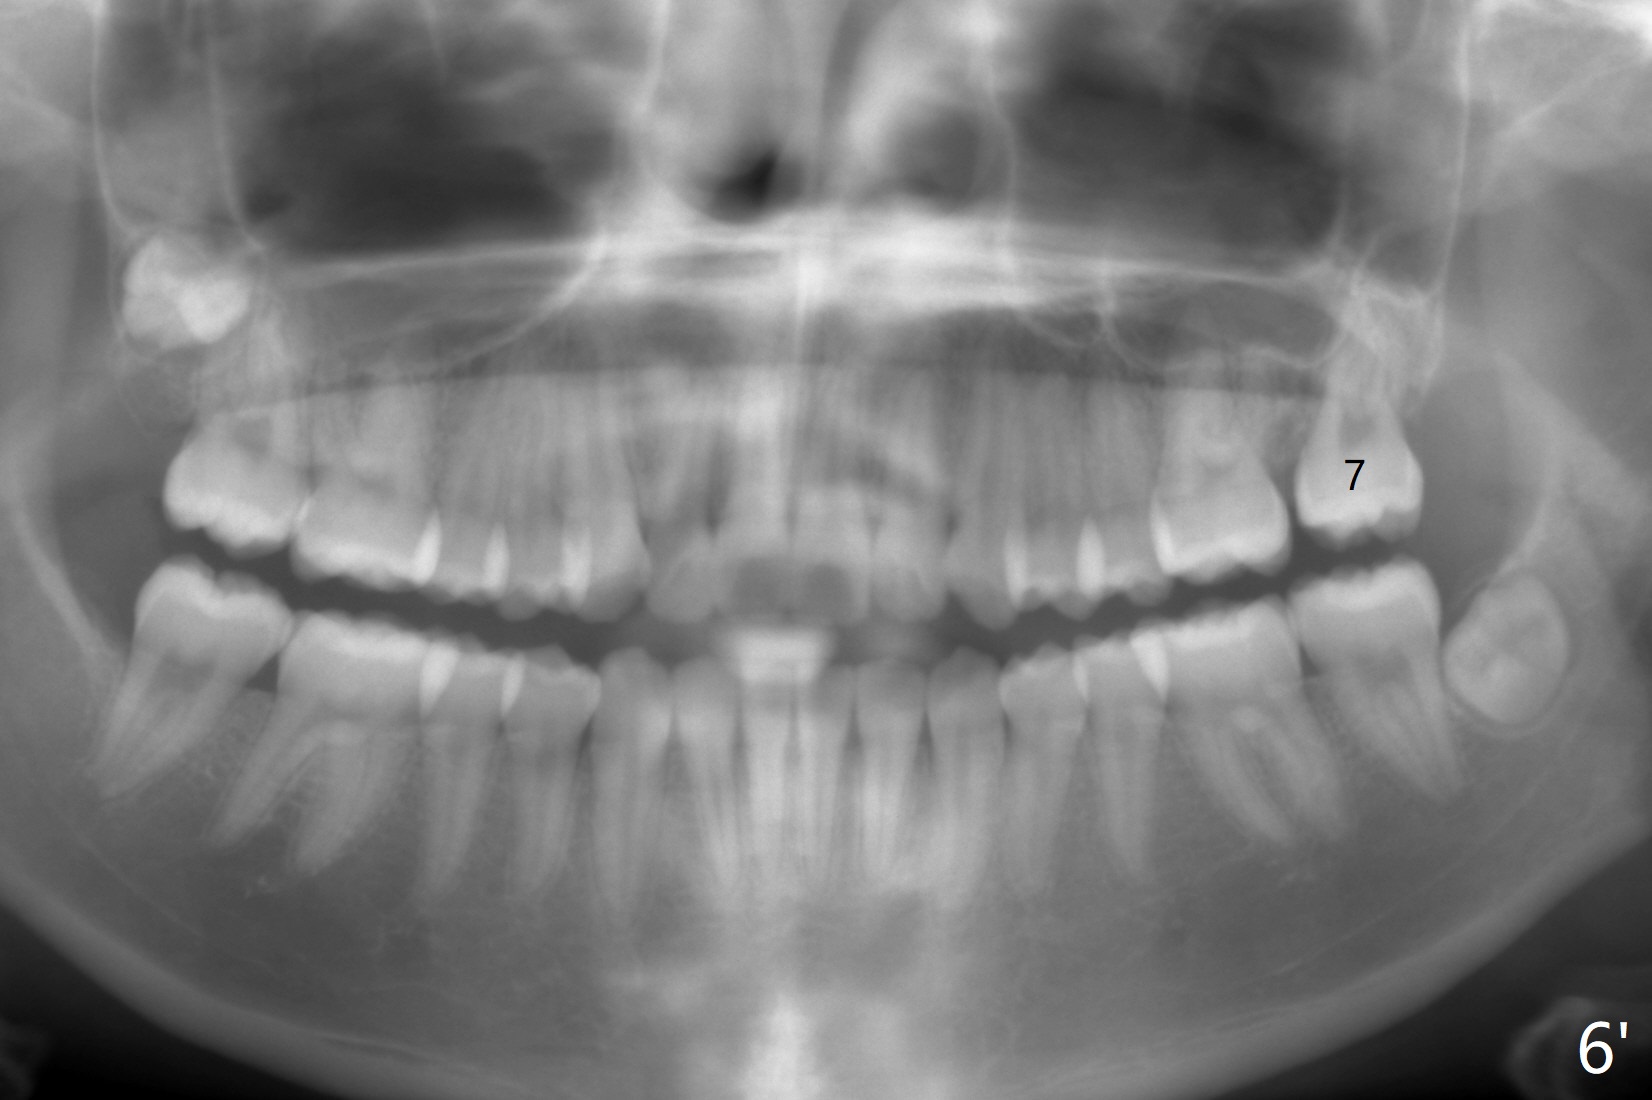

A 12-year-old woman has severe crowding including UL7 impaction (Fig.1-5), finishes non-extraction orthodontics at the age of 15 (Fig.1'-5') and returns for retainer remake at 19 (Fig.1''-5''). Four years post debanding, UL7 (Fig.4') seems to improve its position (Fig.4'').